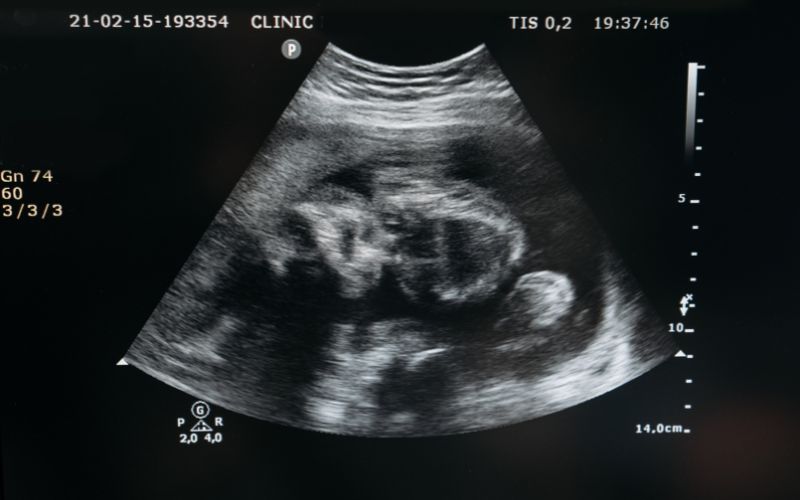

Siêu âm thai là một phương pháp sàng lọc trước sinh được sử dụng rộng rãi trong y khoa ngày nay. Phương pháp này sử dụng sóng âm có tần số cao để thu được hình ảnh thai nhi và nhau thai, tử cung cùng các cơ quan khác nằm trong khung xương chậu. Từ các chỉ số thu được nhờ siêu âm, bác sĩ có thể phân tích, đánh giá được sự phát triển của thai nhi, đồng thời phát hiện ra những bất thường trong bào thai nếu có.

Qua phương pháp siêu âm trắng đen, mức độ phản hồi của các cấu trúc thai mạnh hoặc yếu thì cường độ sáng trên màn hình siêu âm của các cấu trúc sẽ hiển thị khác nhau. Từ đó, bác sĩ có thể phân biệt được các cơ quan, bộ phận,...trên cơ thể thai nhi.